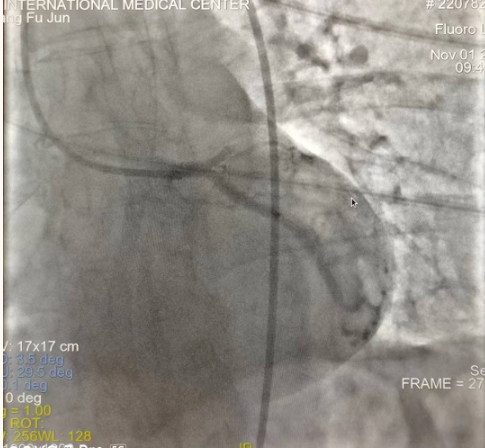

閉塞的血管再通時(shí)間取決于急救時(shí)長(zhǎng)、轉(zhuǎn)運(yùn)時(shí)長(zhǎng)和治療時(shí)長(zhǎng),在前兩方面,醫(yī)院已為患者爭(zhēng)取了最短時(shí)間。患者家屬遠(yuǎn)在陜北,雖然已在趕來(lái)的路上,但最快抵達(dá)西安也要3小時(shí),在與患者家屬電話溝通同意急診手術(shù)后,醫(yī)療總值班代家屬簽字,康曉軍在請(qǐng)示心臟病醫(yī)院王海昌院長(zhǎng)及心臟內(nèi)科CCU尚福軍主任后,積極進(jìn)行術(shù)前準(zhǔn)備。在沒(méi)有家屬陪同、沒(méi)有交費(fèi)、沒(méi)有辦入院手續(xù)的情況下,患者經(jīng)胸痛中心綠色通道被送往心臟冠脈介入手術(shù)室,打通了完全閉塞的心臟前降支近段血管。